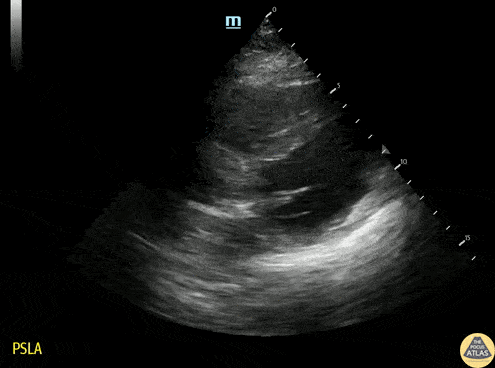

Left Ventricular Dysfunction - Regional Wall Motion Abnormality

60s M presented with L arm and axillary pain for 1 day. EKG with subtle ST elevation in II/III and depression in I, aVL without meeting STEMI criteria. HsTrop elevated to about 25,000. POCUS demonstrated hypokinesis of the inferior and lateral walls. Cardiology felt most c/w NSTEMI and missed inferior MI. TTE confirmed regional wall motion abnormalities, and after medical optimization, pt went to cath lab and had RCA occlusion diagnosed and stented. Dr. Spencer Seballos, PGY1 Denver Health Residency in Emergency Medicine